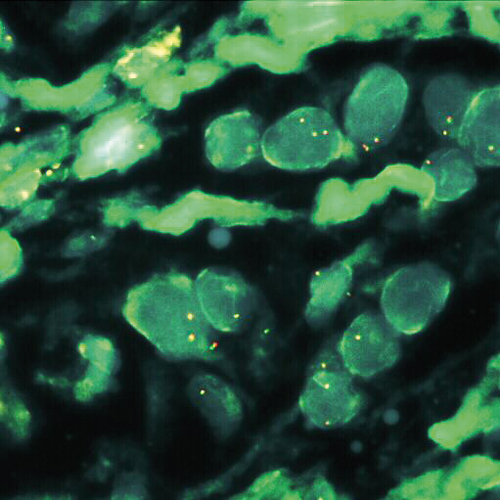

MALT1 (18q21) Break tissue probe hybridized to paraffin embedded material (2RG).

RUO - MALT1 Break (tissue) (18q21)

Low grade malignant lymphomas arising from mucosa associated lymphoid tissue (MALT) represent a distinct clinicopathological entity. The three major translocations seen in MALT lymphomas are t(11;18)(q21;q21) / API2-MALT1, t(14;18)(q32;q21) / IGH-MALT1 and t(1;14)(p22;q32) / IGH-BCL10. A break or split probe for MALT1 (18q21) is best used to analyze translocation of the MALT1 gene on formalin fixed paraffin embedded tissue for routine clinical diagnosis. The MALT1 (18q21) Break probe is optimized to detect translocations involving the MALT1 gene region at 18q21 in a dual-color, split assay. Kreatech has developed this probe for the specific use on cell material (KI-10608), or for the use on tissue (KI-10731).